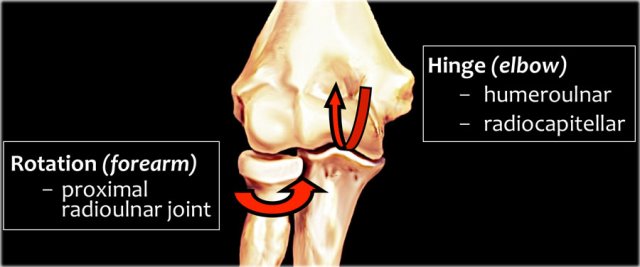

Elbow Mechanics

The elbow serves as a hinge joint when we look at the humeroulnar and radiocapitellar joint.

The other joint is the proximal radioulnar joint with rotation allowing pronation and supination.

Many acute and chronic injuries occur as a result of throwing.

During the throwing motion in the phase of late cocking to acceleration, there are tremendous valgus forces that are pulling the elbow.

The valgus overload results in enormous tension on the medial side trying to pull things apart (yellow arrows), while the lateral side will be under compression (blue arrows).

On the posterior side it causes shear forces along the head of the olecranon (black arrow).